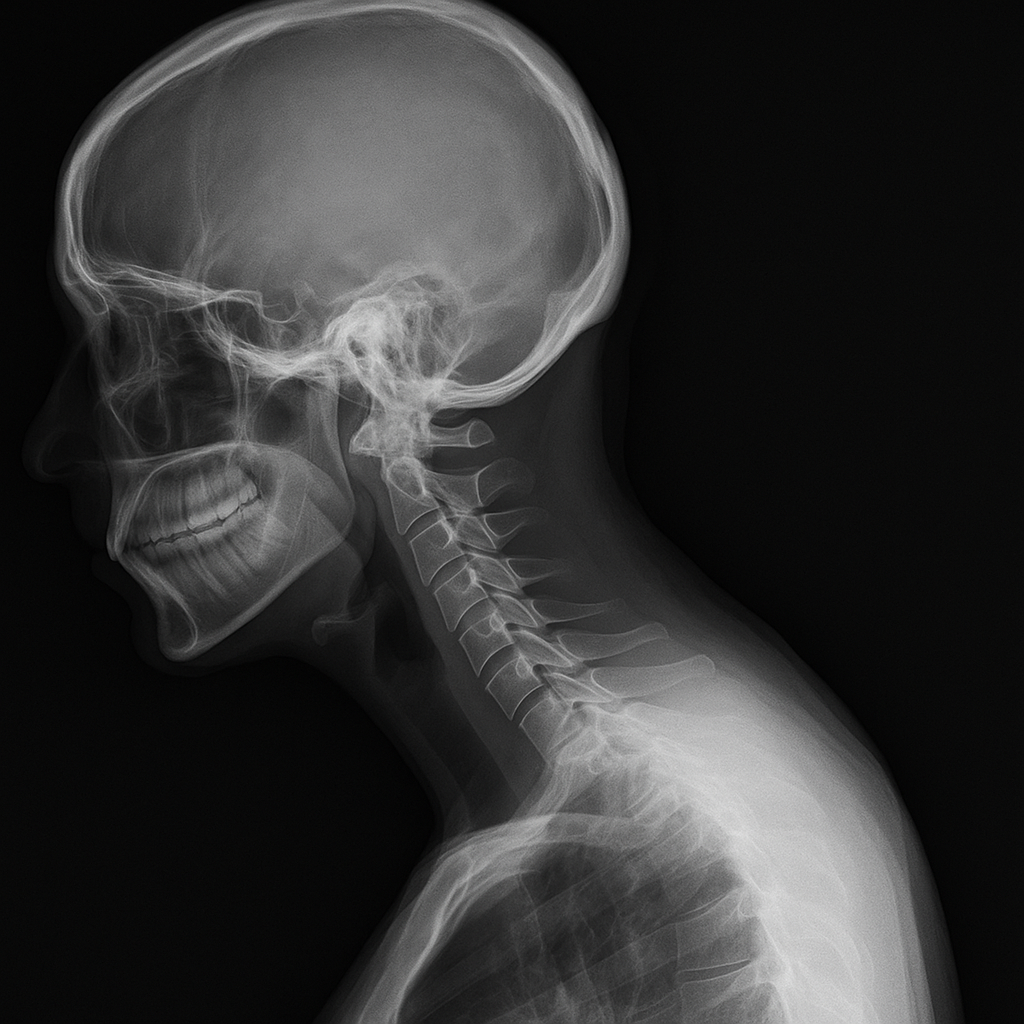

거북목은 정식 명칭으로 ‘전방 머리 자세(Forward Head Posture)’라고 하며,

스마트폰이나 컴퓨터를 오래 사용하면서 목이 앞으로 쭉 튀어나오는 자세를 말합니다.

- 목이 어깨선보다 앞으로 나옴

- 승모근이 긴장해서 뭉침

- 어깨가 안으로 말림

- 턱이 앞으로 나와 이중턱처럼 보이기도 함